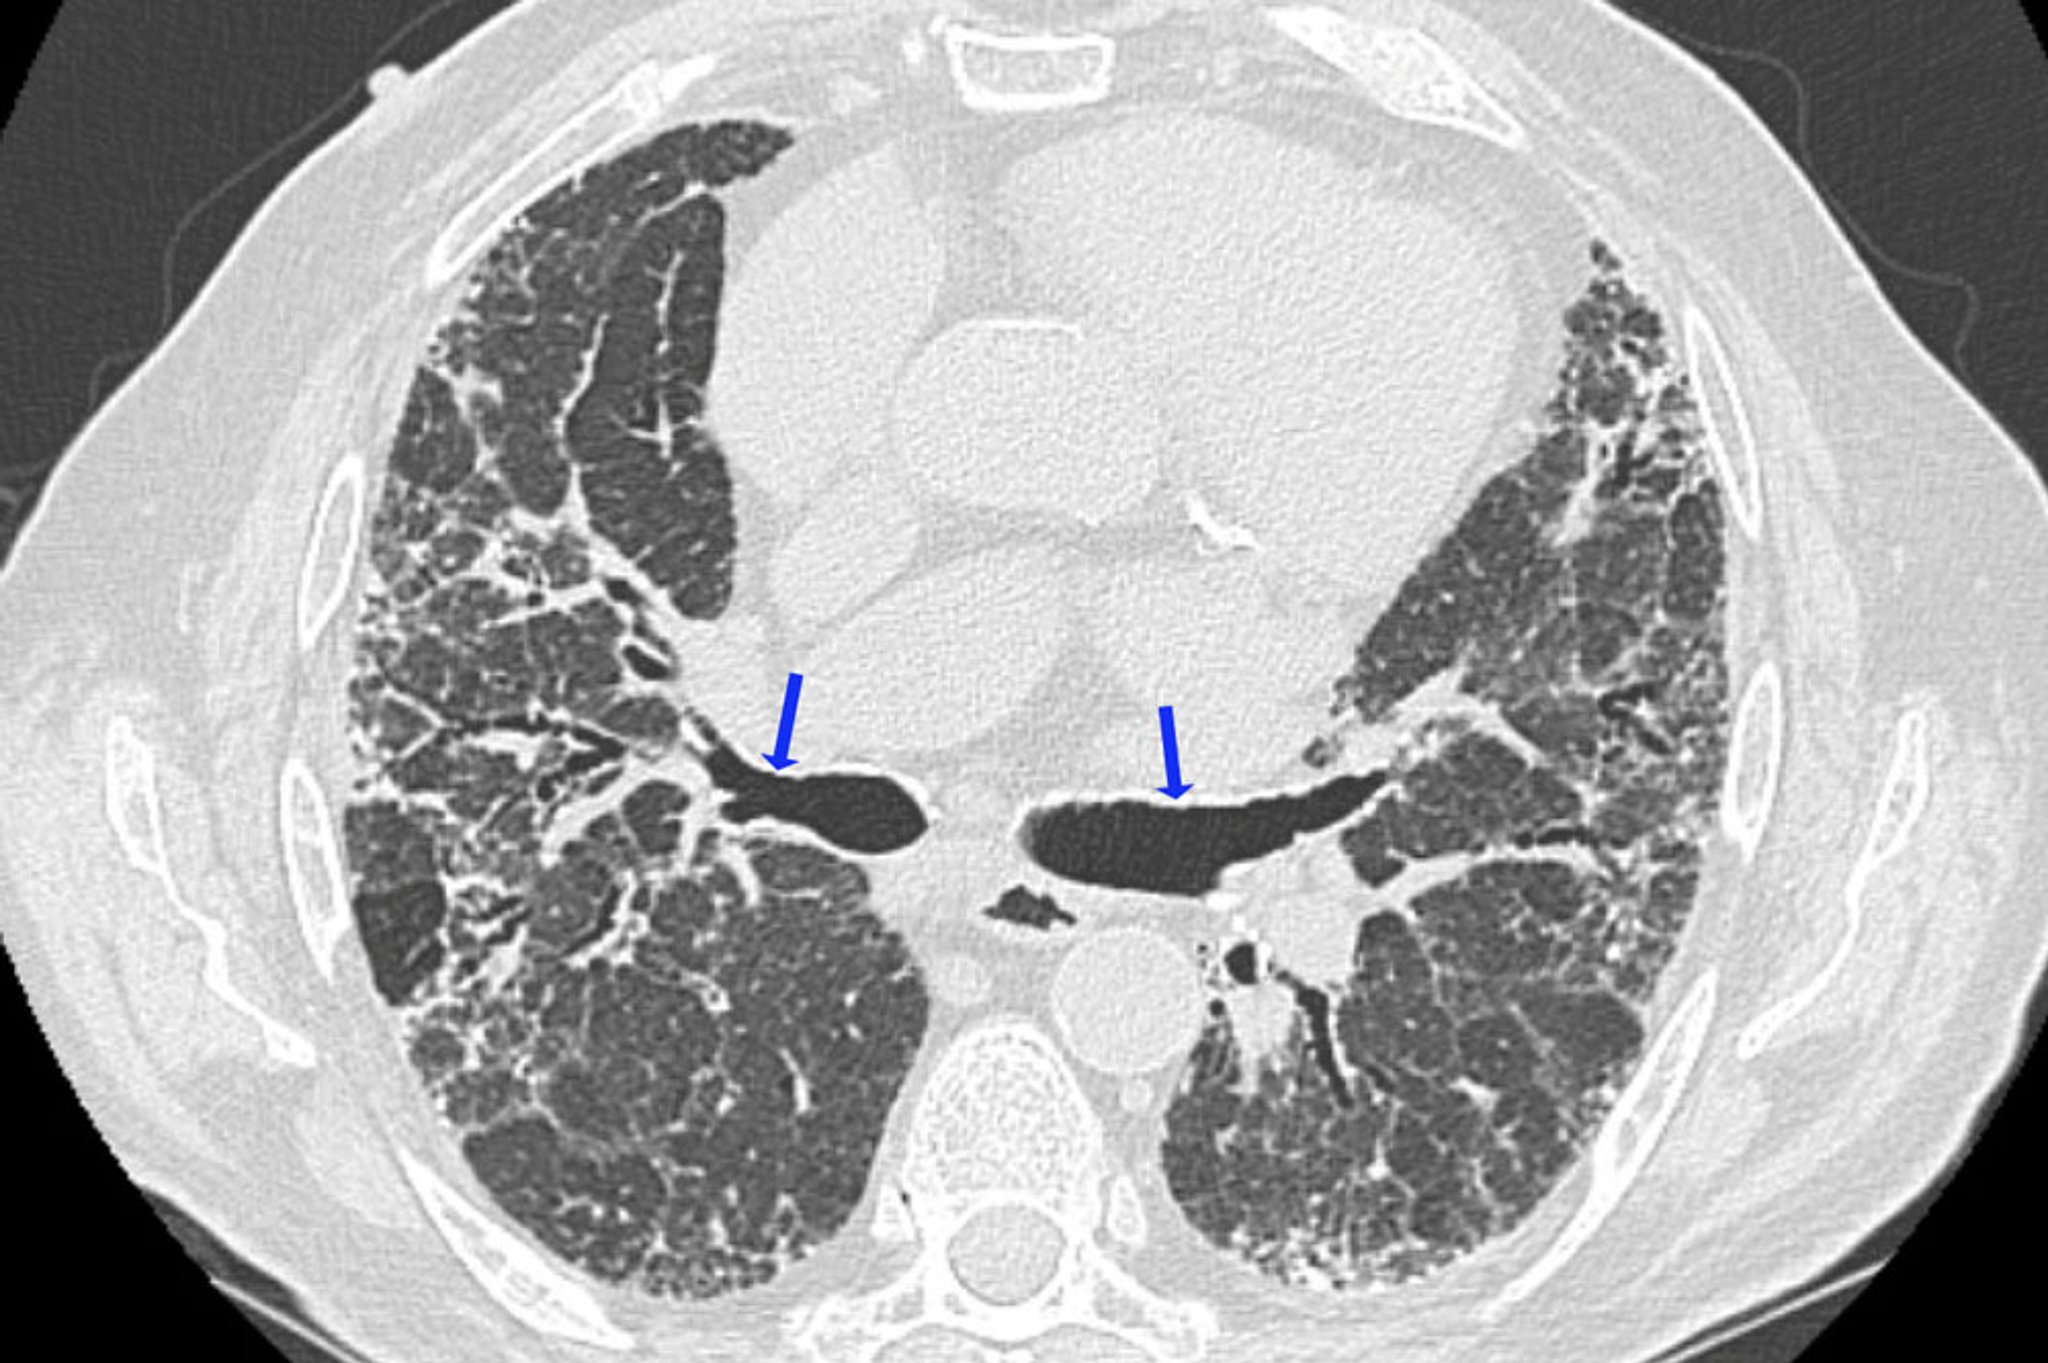

高分辨率CT是评估过敏性肺炎实质改变的首选影像学检查方法,其显示异常的可能性高于标准CT或X线片(2)。

在急性和亚急性过敏性肺炎中,最典型的高分辨率CT表现为小叶中心性微小结节,直径通常小于3毫米,多位于肺小叶中央气道附近。偶尔,磨玻璃影(密度减低)是主要的或有时是唯一的影像学表现。其常为弥散性,但有时不累及次级肺小叶的周围部分。 与闭塞性细支气管炎所见相似的局灶性高透亮区,可能是某些病人的主要特征(例如HRCT呼气相的马赛克影伴空气滞留现象)。

慢性过敏性肺炎有肺纤维化的征象,包括肺叶体积缩小、线状或网状阴影、蜂窝样变和牵拉性支气管扩张。可能出现小叶中心微结节、磨玻璃样密度影和透亮区,但不太明显。一些不吸烟的慢性过敏性肺炎病人有上叶气肿的表现。纵隔淋巴结肿大不常见,由此可将过敏性肺炎与结节病相区别。